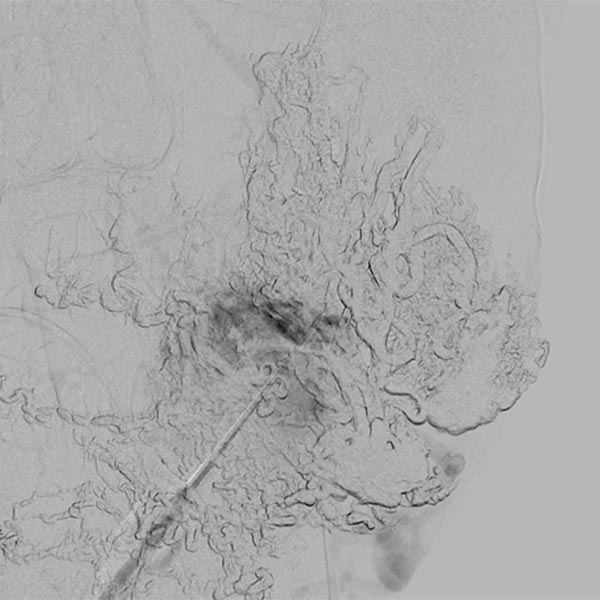

Direct percutaneous puncture of the nidus with a needle in DSA. This direct contrast injection is necessary to verify the correct position of the needle tip before embolization using ethylene-vinyl alcohol copolymer in a direct puncture technique.

Renewed direct puncture of the nidus and DSA to check needle position.

Slow, direct filling of the nidus and draining veins using ethylene-vinyl alcohol copolymer (EVOH) in roadmap technique. Already pre-injected EVOH is subtracted away in this technique and is only visible in outline.